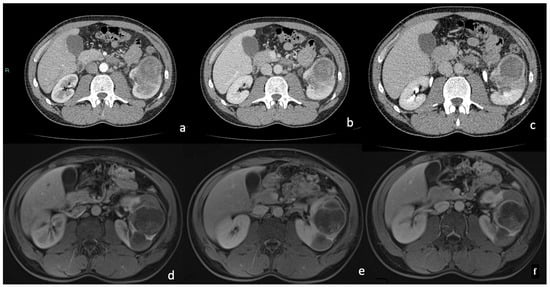

3.3. CT

Density and Contrast Enhancement

- Pre-enhanced phase: 30.3 ± 6.5 HU.

- Arterial phase: 47.2 ± 12.4 HU.

- Venous phase: 64.6 ± 17.3 HU.

- Delayed phase: 61.8 ± 14.5 HU.

3.4. MRI

Signal Intensity, Homogeneity, and Contrast Enhancement

| MRI FEATURES | % | n. | p Value |

|---|---|---|---|

| 85.2% 14.8% | 23 4 | p < 0.05 p > 0.05 |

| 88.9% 7.4% 3.7% | 24 2 1 | p < 0.05 p > 0.05 p > 0.05 |

| 29.6% 11.1% 59.5% | 8 3 16 | p > 0.05 p > 0.05 p < 0.05 |

| 100% | 27 | p < 0.05 |